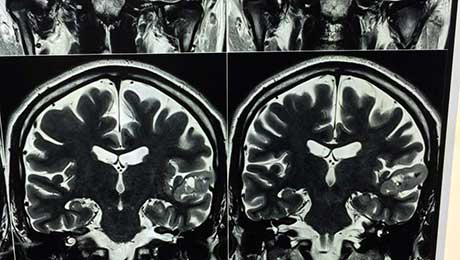

Dnet t2w